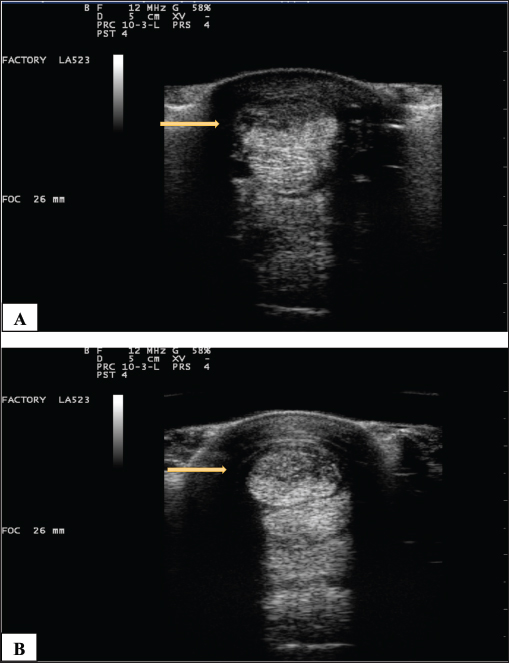

Fig. 7. (A) Pretreatment and B) 70-day post-Tenex® treatment of a severe SDF lesion (arrows).

No adverse events occurred in any case. Results were available from 6 to 41 months (mean, 23.2 months). Follow-up ultrasound imaging demonstrated improvement in fiber alignment and architectural change following treatment in all cases (Fig. 7). All horses had a reduction in lameness from the treated tendon or ligament (AAEP grade 0–1; mean grade 0.2); lameness completely resolved in 8 of 10 treated limbs. All horses returned to their previous level of use. No horses in this study developed a recurrence of their original lesion.